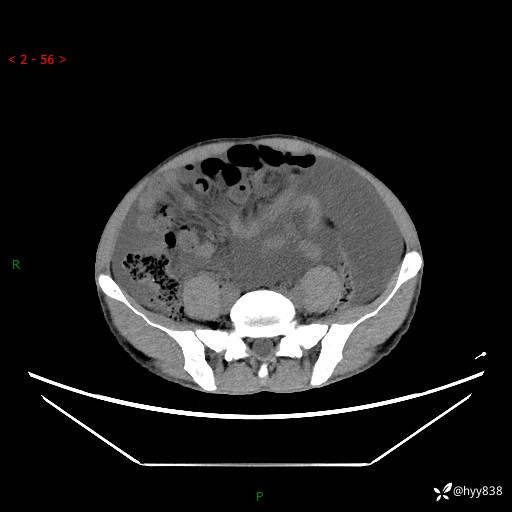

现病史:患者10天前无明显诱因出现腹部胀痛不适,无畏寒发热,无胸痛胸闷,无心慌气短,无恶心呕吐,无腹泻及黑便,无粘液血便及里急后重等症状,4天前在当地县人民医院就诊,行腹部CT示:下腹部占位性病变,腹腔及盆腔积液;今患者为求进一步诊治来我院治疗,门诊以“腹水”收治入院。 发病以来,精神饮食可,大小便正常,体重体力无明显变化。

腹部CT平扫+增强